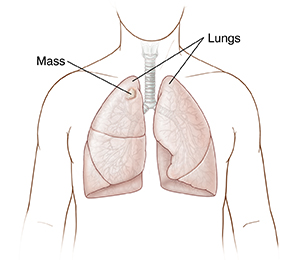

Masses

A mass is a lump of abnormal tissue. It can be tissue that's not cancer (benign). Or it can be cancer (malignant). If a mass is found in the lung or chest, the health care provider will want to take a tissue sample (biopsy) of it. This tissue sample helps the provider find if the mass is cancer. The mass may need to be removed even if it's not cancer.